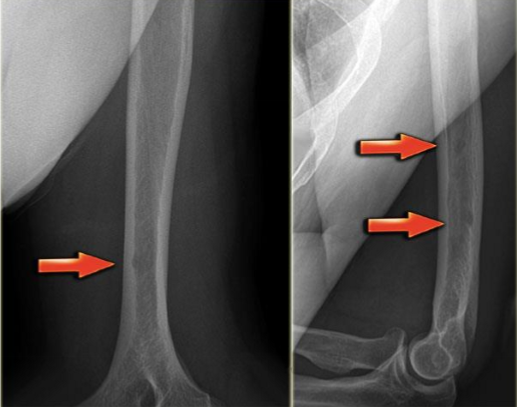

conventional X-ray

obtained with at least 2 views exposed at 90° to each other (orthogonal views)

cannot visualize entire circumference of a tubular bone